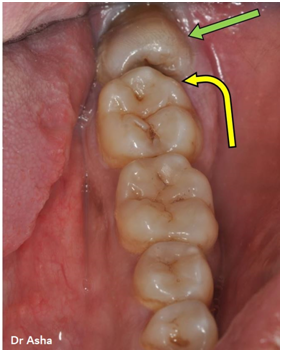

This photo shows a wisdom tooth (green arrow) huddled behind the 2 nd molar. The wisdom tooth is lying on its side and jammed – or impacted – against the tooth in front of it.

Food debris can collect in the groove (yellow arrow) between the two teeth. This groove is almost impossible to clean

Decay can develop in hidden areas between the teeth.

In the early stages, such decay is often undetected as there is no pain.

Left alone, the decay will grow.